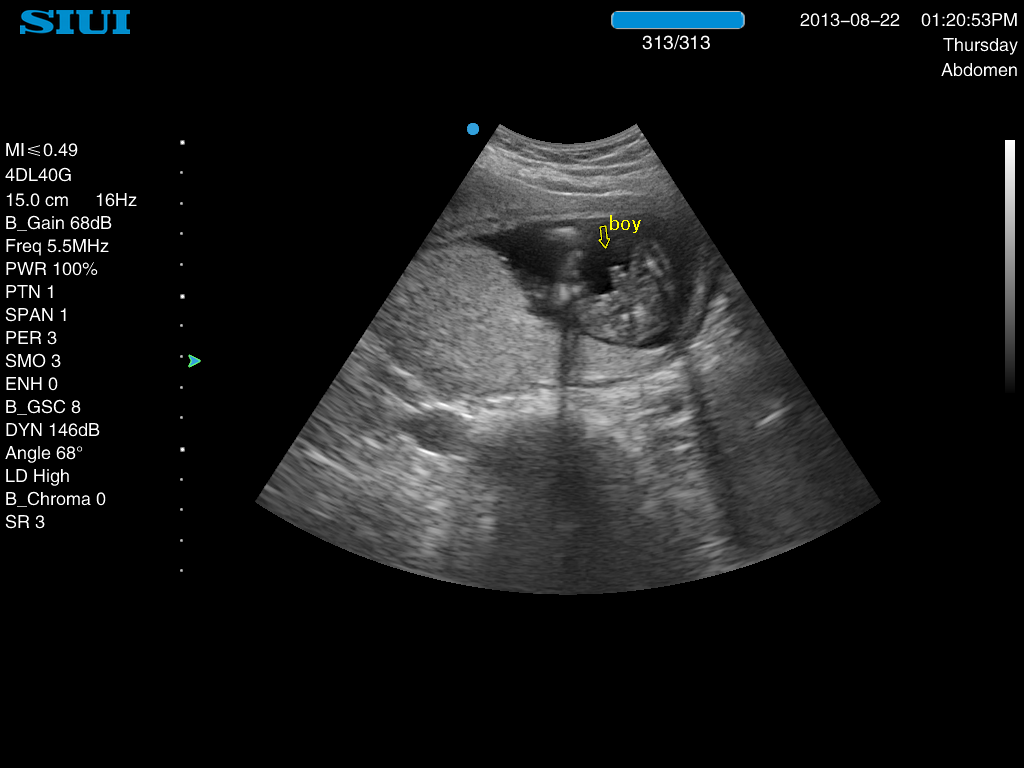

Attachment 13365So here is my 17wk ultrasound pic..... He is all boy as you can see!

I had put my 12wk 6day pic up for guesses and everyone guessed girl... but the technician looked at the pic and said that there is no actual nub in the 12wk pic, but she can see how people (incl me) thought it looked like a girl nub

So there you go... boy #4 on the way for me!!:oops: